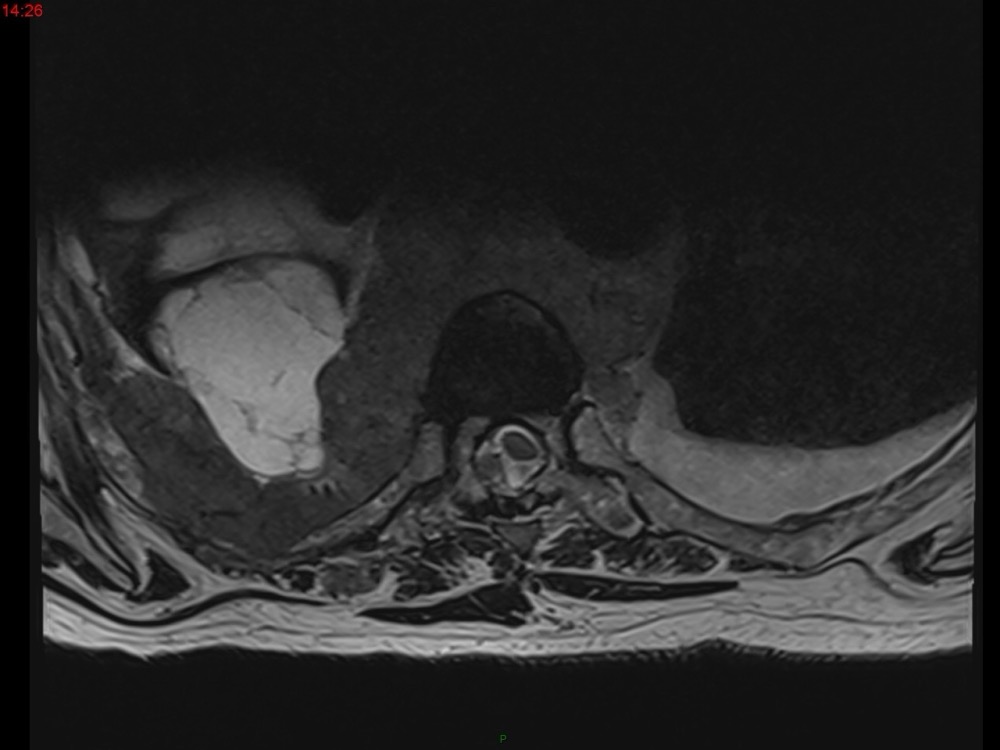

Marie Pauline Talabard 11/01/2023